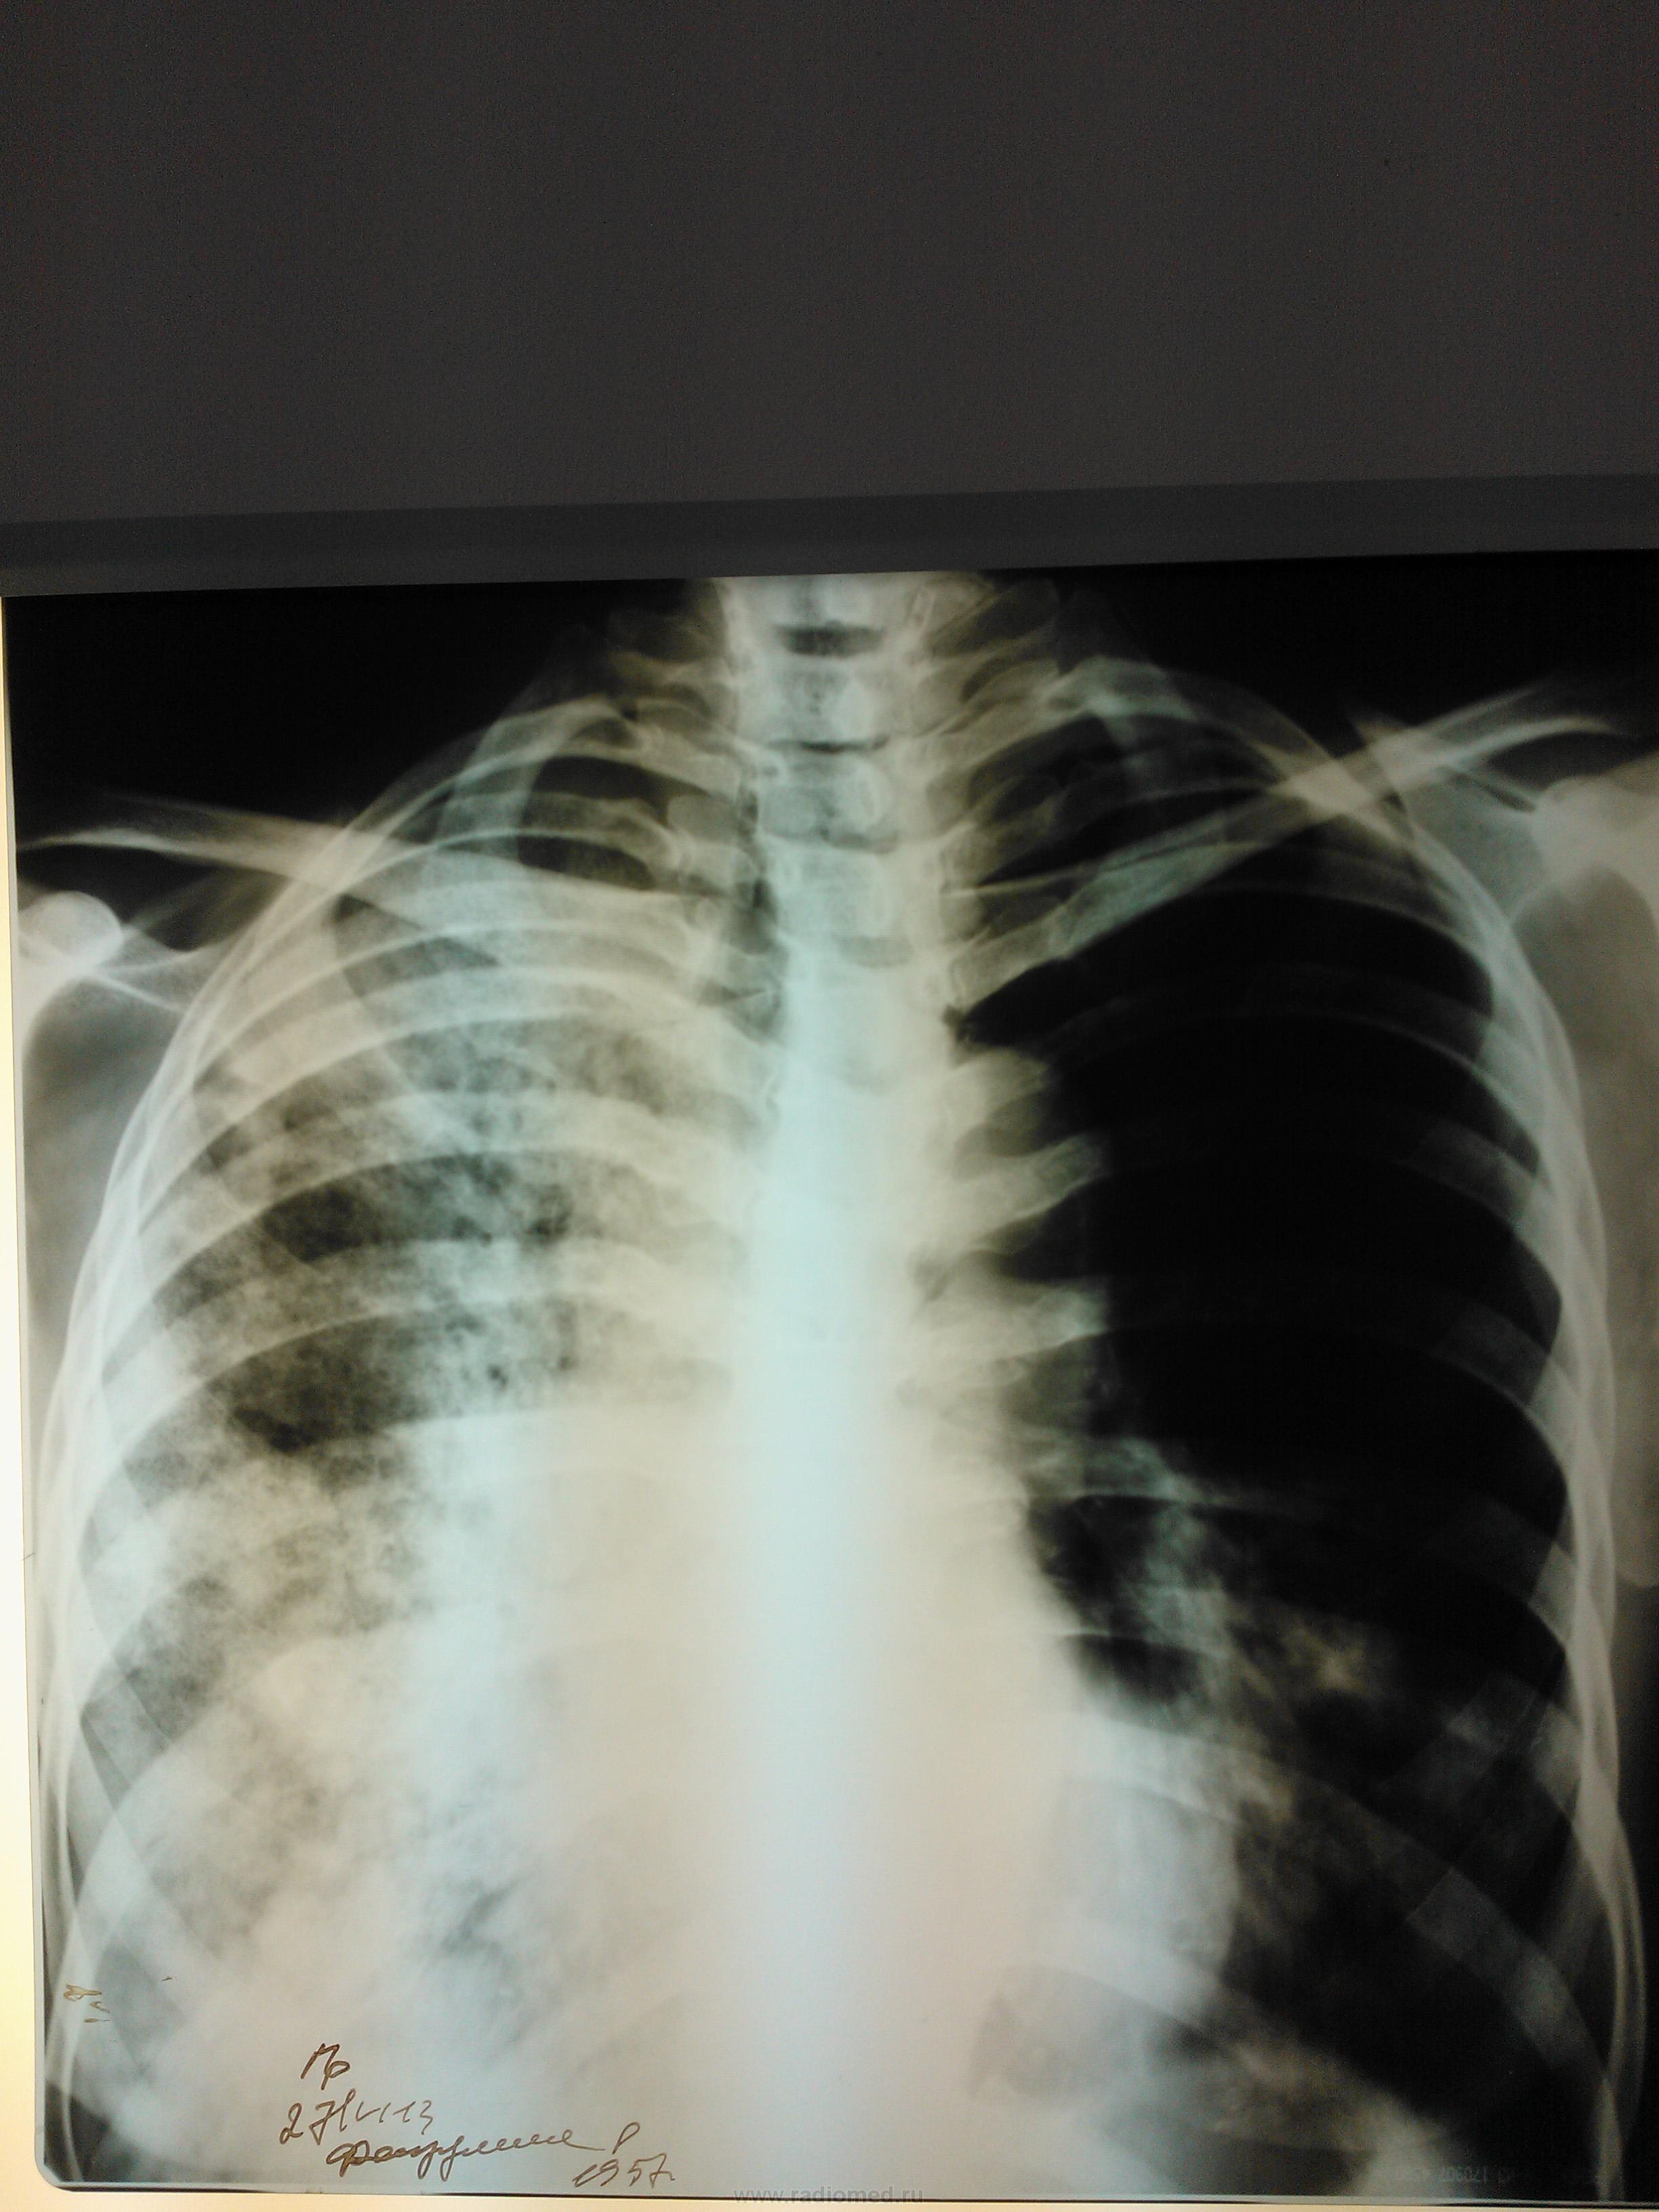

Женщина пенсионного возраста поступила в отделение сестринского ухода при терапии с диагнозом "Алкогольная интоксикация", жалоб особых нет, раннее не обследована, из анамнеза злоупотребление алкоголем. после проф. флюшки отправлена на консультацию к онкологу и фтизиатру. фтизиатр свое исключает и также отправляет к онкологу, онколог рекомендует КТ ОГК, на КТ врят ли поедет так как из глухой деревни, в анализах крови ничего особенного, хотеллось бы узнать мнения коллег по данному случаю.

Начинаем диф ряд от рака, формирующегося абсцесса и тбц.

Любой рентгенлаборант способен, при синдроме затемнения в легком, построить дифряд: пневмония? туберкулез? рак?

Случай достаточно непростой. Сразу обратил внимание на выраженую компенсаторную эмфизему левого легкого. Правое значит очень плохо функционирует. И причиной этого может быть и обширность поражения, и бронхообструкция, и то и другое вместе. Полости могут быть и при туберкулёзе, и при абсцедирующей прневмонии, и при раке с распадом. Абсцесс вроде бы не вписывается в лабораторные показатели, но у хронических алкоголиков может быть убитый иммунитет. Туберкулез, на мой взгляд, при такой обширности, должен был дать отсев и в другое легкое. Так что, из этих рассуждений больше склоняюсь к раку. В таком неоднозначном случае всеравно следует оставить диф. ряд: рак, тбц, абсцедирующая пневмония и уговорить пациента на КТ, бронхоскопию.

По-моему это типичная картина активного туберкулеза - инфильтраты со склонностью к слиянию, очаги с нечеткими контурами.. Средостение смещено вправо, что может указывать на фиброз в правом легком.. Спокойные анализы, неяркая клиника туда же - к туберкулезу. На каком основании фтизиатр так быстро сказал, что это не его?

Если это туберкулёз, то "по картинке" вероятнее всего казеозная пневмония..., а палок, при таком предположении должно быть "океян - море".

А где же центральный рак на боковом снимке? Все те же инфильтраты, опухолевой массы не видно.. Тем более по-моему начинается обсеменение нижних отделов левого легкого.. Неужели больше нет сторонников тбц. Если на КТ не доедет, то пусть хоть мокроту как следует соберут посмотрят

В общем, коллеги, обычное дело: лечить как пневмонию, обследовать на туберкулез, в уме держать рак.

Никак нельзя исключить казеозную пневмонию правого легкого с отсевами в нижнюю долю левого легкого . Нужны снимки в динамике. (бывший фтизиатр, в настоящем- рентгенолог). В мокроте КУМ не сразу может выделить.

ИМХО: все ставят на первое место казеоную пневмонию ( устаревшее название скоротечная чахотка).Но, при этом клиника отсутствует и верхушки лёгких с 2-х сторон отностельно чистые. Ещё с версией туберкулёза с обычным течением , когда могут отсутствовать жалобы, можно согласиться, но в вариант казозной (т.е. дестуктивной )ПНЕВМОНИИ , вериться с трудом.

Формально по рентгенограммам, особенно прямой, в первую очередь, на мой взгляд, можно подумать о гангрене правого лёгкого. Правда такой диагноз у многих вызывает неприятие.

сегодня пациентке провели контрольную R-графию (снимок только в прямой проекции и на другом аппарате - немного "мягче", предыдущий сломался, а этот боковой не смог снять), сравнить тяжело (на разных аппаратах, разная экспозиция и тд и тп) но по мне динамика отрицательная.